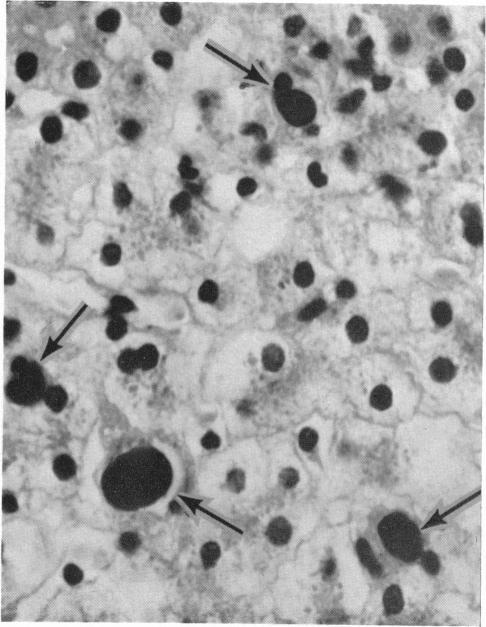

Acute alcoholic hepatitis.